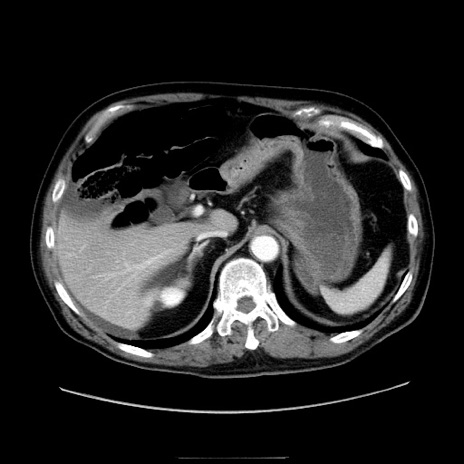

症例30(横断像)

冠状断像

【症例】80歳代男性

【主訴】臍周囲痛

【現病歴】約6時間前から臍下部痛が出現。次第に腹部膨隆・背部痛も生じてきたため来院。背部痛の場所は変化しない。

【身体所見】意識清明、BT 36.3℃、BP  131/87mmHg、P 87bpm、SpO2 100%(RA)、臍周囲自発痛・圧痛あり、反跳痛なし、自発痛部位に一致して板状硬あり、腹部膨隆、腸雑音減弱、CVA tenderness両側陰性。

【データ】WBC 19600、CRP 0.33